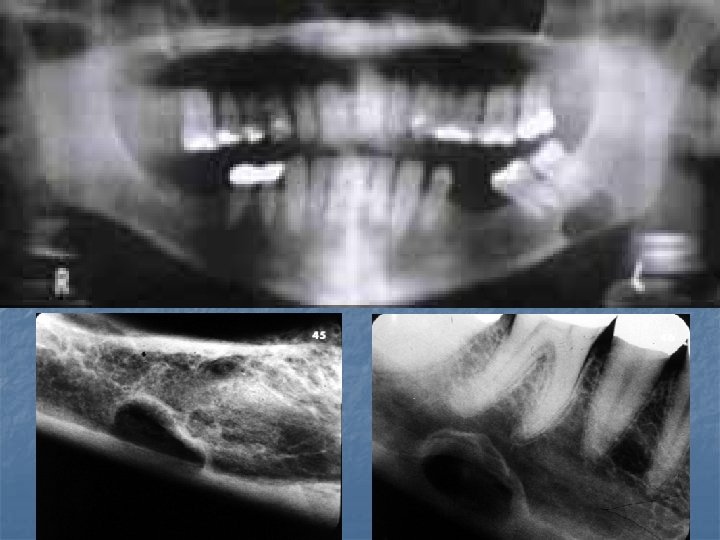

Torus Mandibularis n n n A common exostosis that develops along the lingual portion of the mandible. Above the mylohyoid in the premolar region, bilateral in 90% of cases. Can appear on periapical radiographs superimposed over the roots of the teeth. Prevalence 5 -40% depending on the study, more common in Asians and Inuit. Prevalence peaks in early adult life and tapers in later years. It also correlates with bruxism and remaining teeth which supports it’s response to functional stress. Surgery may be needed to accommodate a lower denture.

Stafne Defect n n Asymptomatic radiolucent lesionlocated near the angle of the mandible that represents a concavity of the cortical bone caused by the submandibular gland. It is below the IDN between the molar teeth and the angle of the mandible